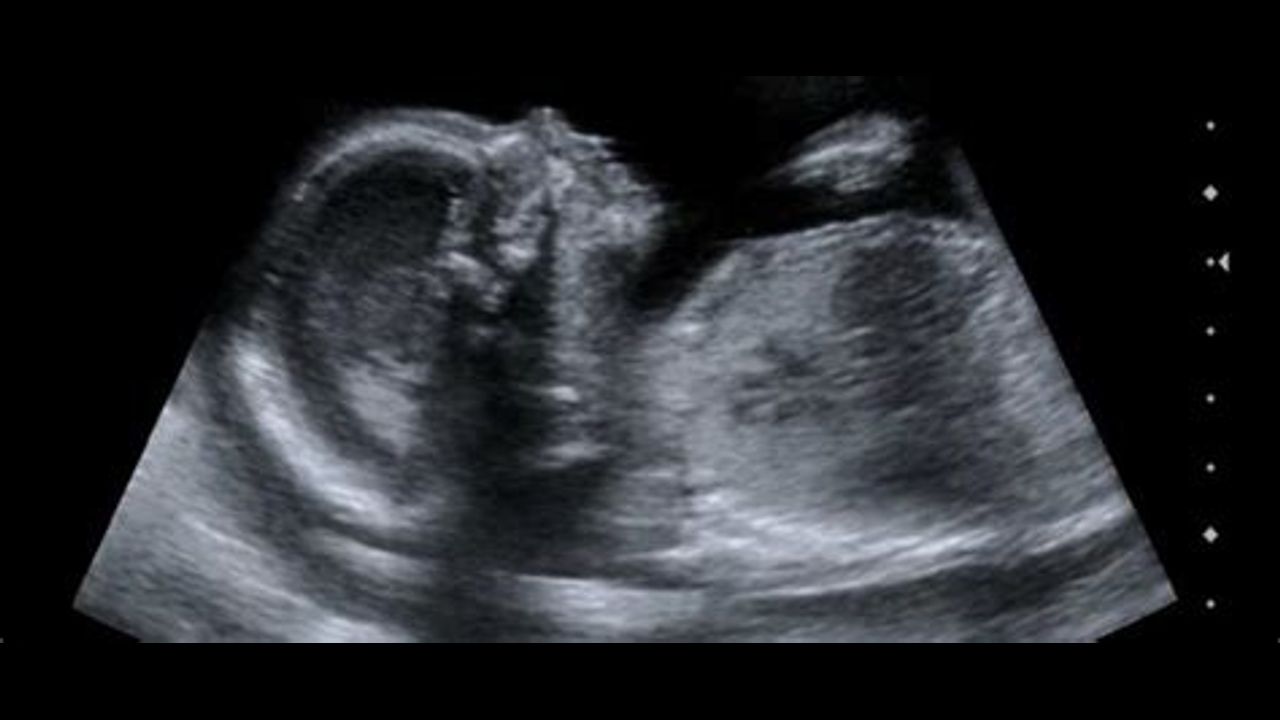

Stew Peters Interviewing Deanna Lorraine, 82% Of Pregnant Women In Study Had Miscarriage, After Receiving The Vaccination